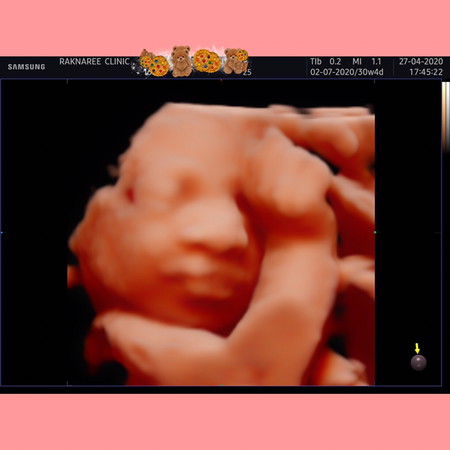

อัลตราซาวด์4มิติ

27/4/63 วันนี้ได้เจอหน้ากันครั้งแรกแบบชัดๆ มีแอบบ้าง เอามือบังบ้าง ได้เห็นแค่นี้ก็ดีใจแล้วจ้า อยากแนะนำคุณแม่ๆคนไหนที่จะอัตราซาวด์ทั้ง2หรือ 4มิติ แนะนำที่นี้เลยค่ะ ที่นี้ดูแลดีมากค่ะ ทั้งหมอ พยาบาล ร้านสะอาด ปกติจะซาวดูแถวบ้าน หมอไม่ได้ดูแลดีแบบนี้ เจอที่นี้แล้วประจับใจค่ะ ไม่ได้มีส่วนเกี่ยวข้องอะไรนะคะ ตามมาจากเพจเฟสบุ้คดีเลยอยากบอกต่อ คลีนิกอยู่แถวเซ็นทรัลแจ้งฯ